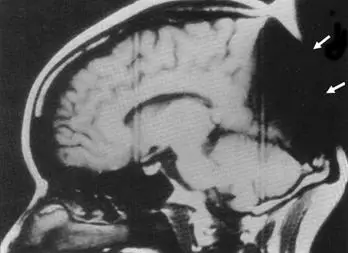

本題附圖為矢狀切面(sagittal)腦部 MRI 影像,圖中兩支白色箭號(↗↗)指向影像左上方頭皮/枕部區域,可見一局部暗色訊號缺失區(signal void),該區域呈明顯低訊號(黑色),且邊界清楚。此種局部訊號缺失並非腦組織病變,而是由頭皮附近的金屬異物(如髮夾、釘書針、手術夾等金屬物品)引起的磁感性假影(magnetic susceptibility artifact)。

訊號缺失的機制為:金屬物質的磁感率(magnetic susceptibility)與周遭組織差異甚大,導致局部磁場不均勻(magnetic field inhomogeneity),引發自旋去相(T2* dephasing),產生幾何失真(geometric distortion)與訊號缺失;梯度回音(gradient echo, GRE)序列及磁感率加權影像(suscept